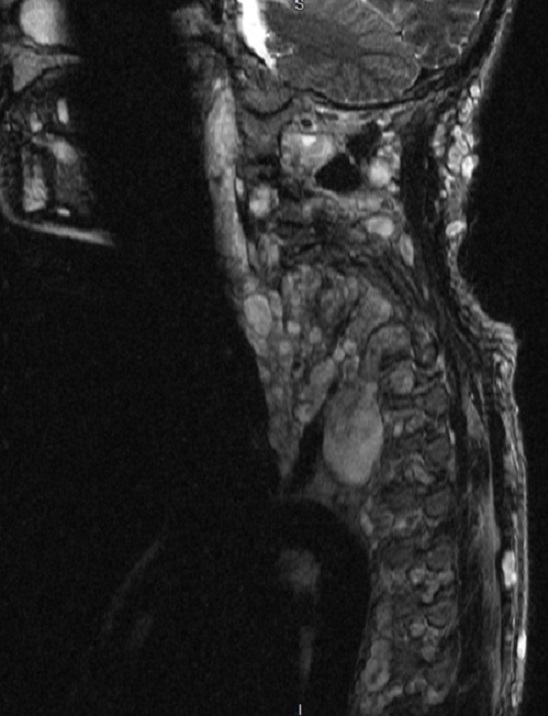

A 67-year old woman with chronic hypertension, hyperlipidemia and diabetes mellitus non-compliant to medication presented with a 10-day history of recurrent visual phenomena in the left visual field. She described stationery multi-coloured flashing lights which decreased in intensity, brightness and size after 3 minutes. She was alert and conscious during attacks. There was no limb jerking. Neurological examination was normal with no visual field defect. Capillary glucose was 28.1 mmol/L, Hba1c 9% and B-hydroxybutyrate < 0.1. She was treated with actrapid 8 units, glipizide 5 mg BD and empagliflozin 12.5 mg OM. Interictal electroencephalogram was normal with no epileptiform activity. Brain magnetic resonance imaging revealed restricted diffusion in the right occipital cortex with corresponding cortical thickening and increased FLAIR signal with subtle hypodensity on GRE sequence. Her visual symptoms improved dramatically with hydration and diabetic control. She was treated with a short course of keppra. One month later repeat MRI brain showed resolution of the DWI and FLAIR abnormalities.

Initial dwi

D